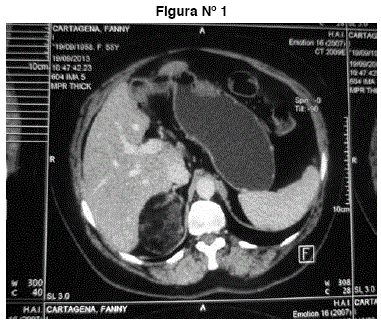

TAC abdomen y pelvis: tumor suprarrenal derecho heterogéneo redondeado, hipodenso con coeficiente de atenuación -38 UH grasa. Mide 66 mm. No adenopatías, no líquido libre, no otros tumores. Imágenes 1 y 2.

Figuras N° 1 y N° 2. Tumor suprarrenal derecho heterogéneo redondeado, hipodenso con coeficiente de atenuación -38 UH grasa. Mide 66 mm. No adenopatías, no líquido libre, no otros tumores.